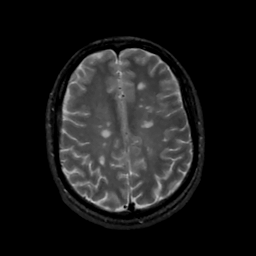

MR Study #15, June 9, 1991 -- Slice #35

[Home][Help][Clinical][Tour 1][Tour 2] Slice 35